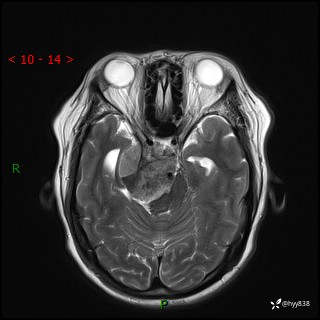

颅脑MRI平扫+增强